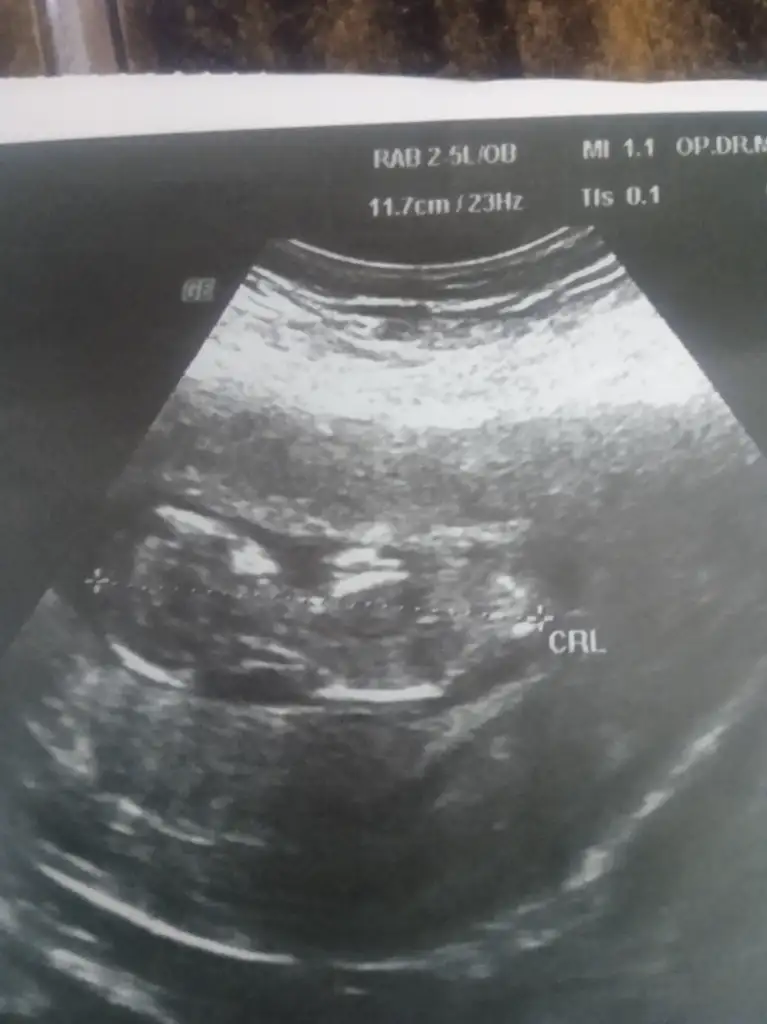

Merhaba kızlar bugün 12+5 günlük olduk normalde devlet Hastanesi'ne gidiyorum geçen hafta bebeğimi kıza benzetti bugün düşük tehlikem olduğu için bide özele muayane olayım dedim belki daha çok ilgilenir diye ama sinir krizi geçirdim resmen devlet hastanesindeki doktor bu doktordan iyi çıktı en azından benimle anlaşılır bir şekilde konuşuyor. Bugün düşük tehlikem devam ediyormu dedim bana ben içerdeki kanamayı nasıl bileyim dedi şuan yok derim bı cikarsin odadan 5 dakika sonra belki düşük yaparsın dedi neye uğradığını şaşırdım sonra cinsiyeti sordum merakimdan bu haftada cinsiyeti bellimi olur dedi niye başka özel hastanelerde belli olan çok dediğimde çok erken dedi anlayan varmı rica etsem ??

1 hafta önceydi canım gittigimde kıza benziyor dedi bende kız istiyorum zaten kanama alanı kesenin altında hala devam ediyor bu büyüklükte kalsa iyi dedi ama sen yine ilaçlarını iç bol bol istirahat et dedi bugünki sözde özel olan doktor neyi göremedi neye göre konuştu hiç anlamis değilim

Kızlar bunlar 6 8 ve 11 haftanın ultrasonlari anlayan varmı ?